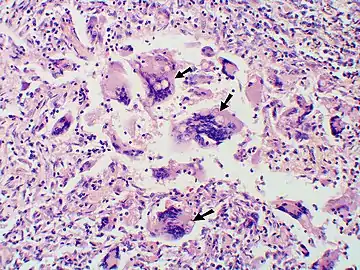

- Large yeast-like fungi seen within giant cells at arrows.

- Large yeast-like fungi seen within giant cells at arrows. Budding yeasts in cytoplasm of giant cells at arrows. Broad-based budding and double contoured cell wall seen in the giant cell in the center is characteristic of Blastomyces dermatitidis.